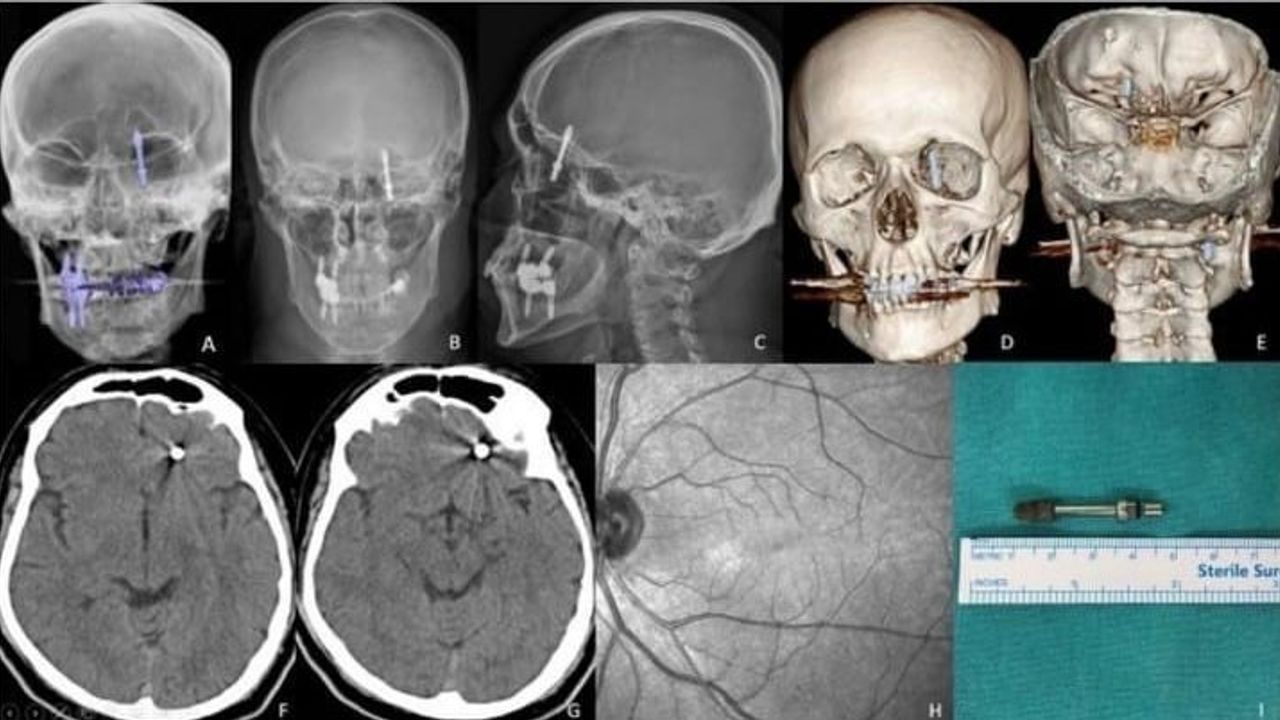

Baygınlık geçiren Yılmaz, kliniğin kendi aracıyla hastaneye kaldırıldı. Tomografi çekiminde vidanın beynine kadar ilerlediği ortaya çıktı. Acil ameliyata alınan talihsiz adam, saatler süren operasyonla ölümden döndü.

Nilüfer ilçesinde özel bir diş kliniğinde muayene olan Yılmaz’a, dişlerinin sallandığı gerekçesiyle implant tedavisi önerildi. Ancak iddiaya göre, doktor A.D.’nin hatalı müdahalesi sonucu implant vidası çene kemiğini delip kafatasına saplandı.